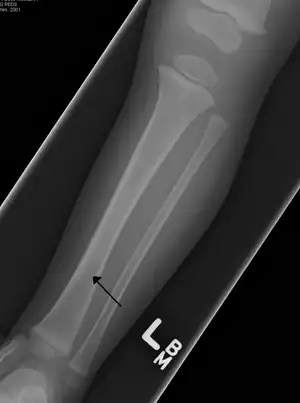

Toddler's fracture

Toddler's fractures are bone fractures of the distal (lower) part of the shin bone (tibia) in toddlers (aged 9 months-3 years) and other young children (less than 8 years).[1] The fracture is found in the distal two thirds of the tibia in 95% of cases,[1] is undisplaced and has a spiral pattern. It occurs after low-energy trauma, sometimes with a rotational component.

| A toddler's fracture | |

Typical symptoms include pain, refusing to walk or bear weight and limping -bruising and deformity are absent. On clinical examination, there can be warmth and swelling over the fracture area, as well as pain on bending the foot upwards (dorsiflexion). The initial radiographical images may be inconspicuous (a faint oblique line) and often even completely normal.[3] After 1–2 weeks however, callus formation develops. The condition can be mistaken for osteomyelitis, transient synovitis or even child abuse. Contrary to CAST fractures, non-accidental injury typically affect the upper two-thirds or midshaft of the tibia.